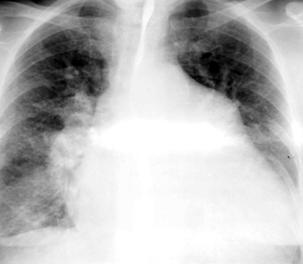

4.RX

:

Cardiomegalie implicand in special AS,VS,rareori VD.Circulatie pulmonara incarcata.Gradul cardiomegaliei si cresterea circulatiei pulmonare sunt direct relationate cu magnitudinea suntului.

In BPVO AP si ramurile sunt f.dilatate,dar periferia pulmonara este ischemica.